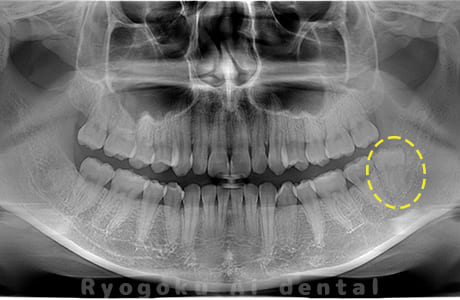

Case04

-

- 原因

- 上顎の親知らず、下顎の水平埋伏の親知らず

- 治療内容

- 上顎の親知らず、下顎の水平埋伏の親知らずを抜歯したケースです。

<リスク・副作用>

手術後は痛み、腫れ、痺れなどの副作用が生じる場合があります。